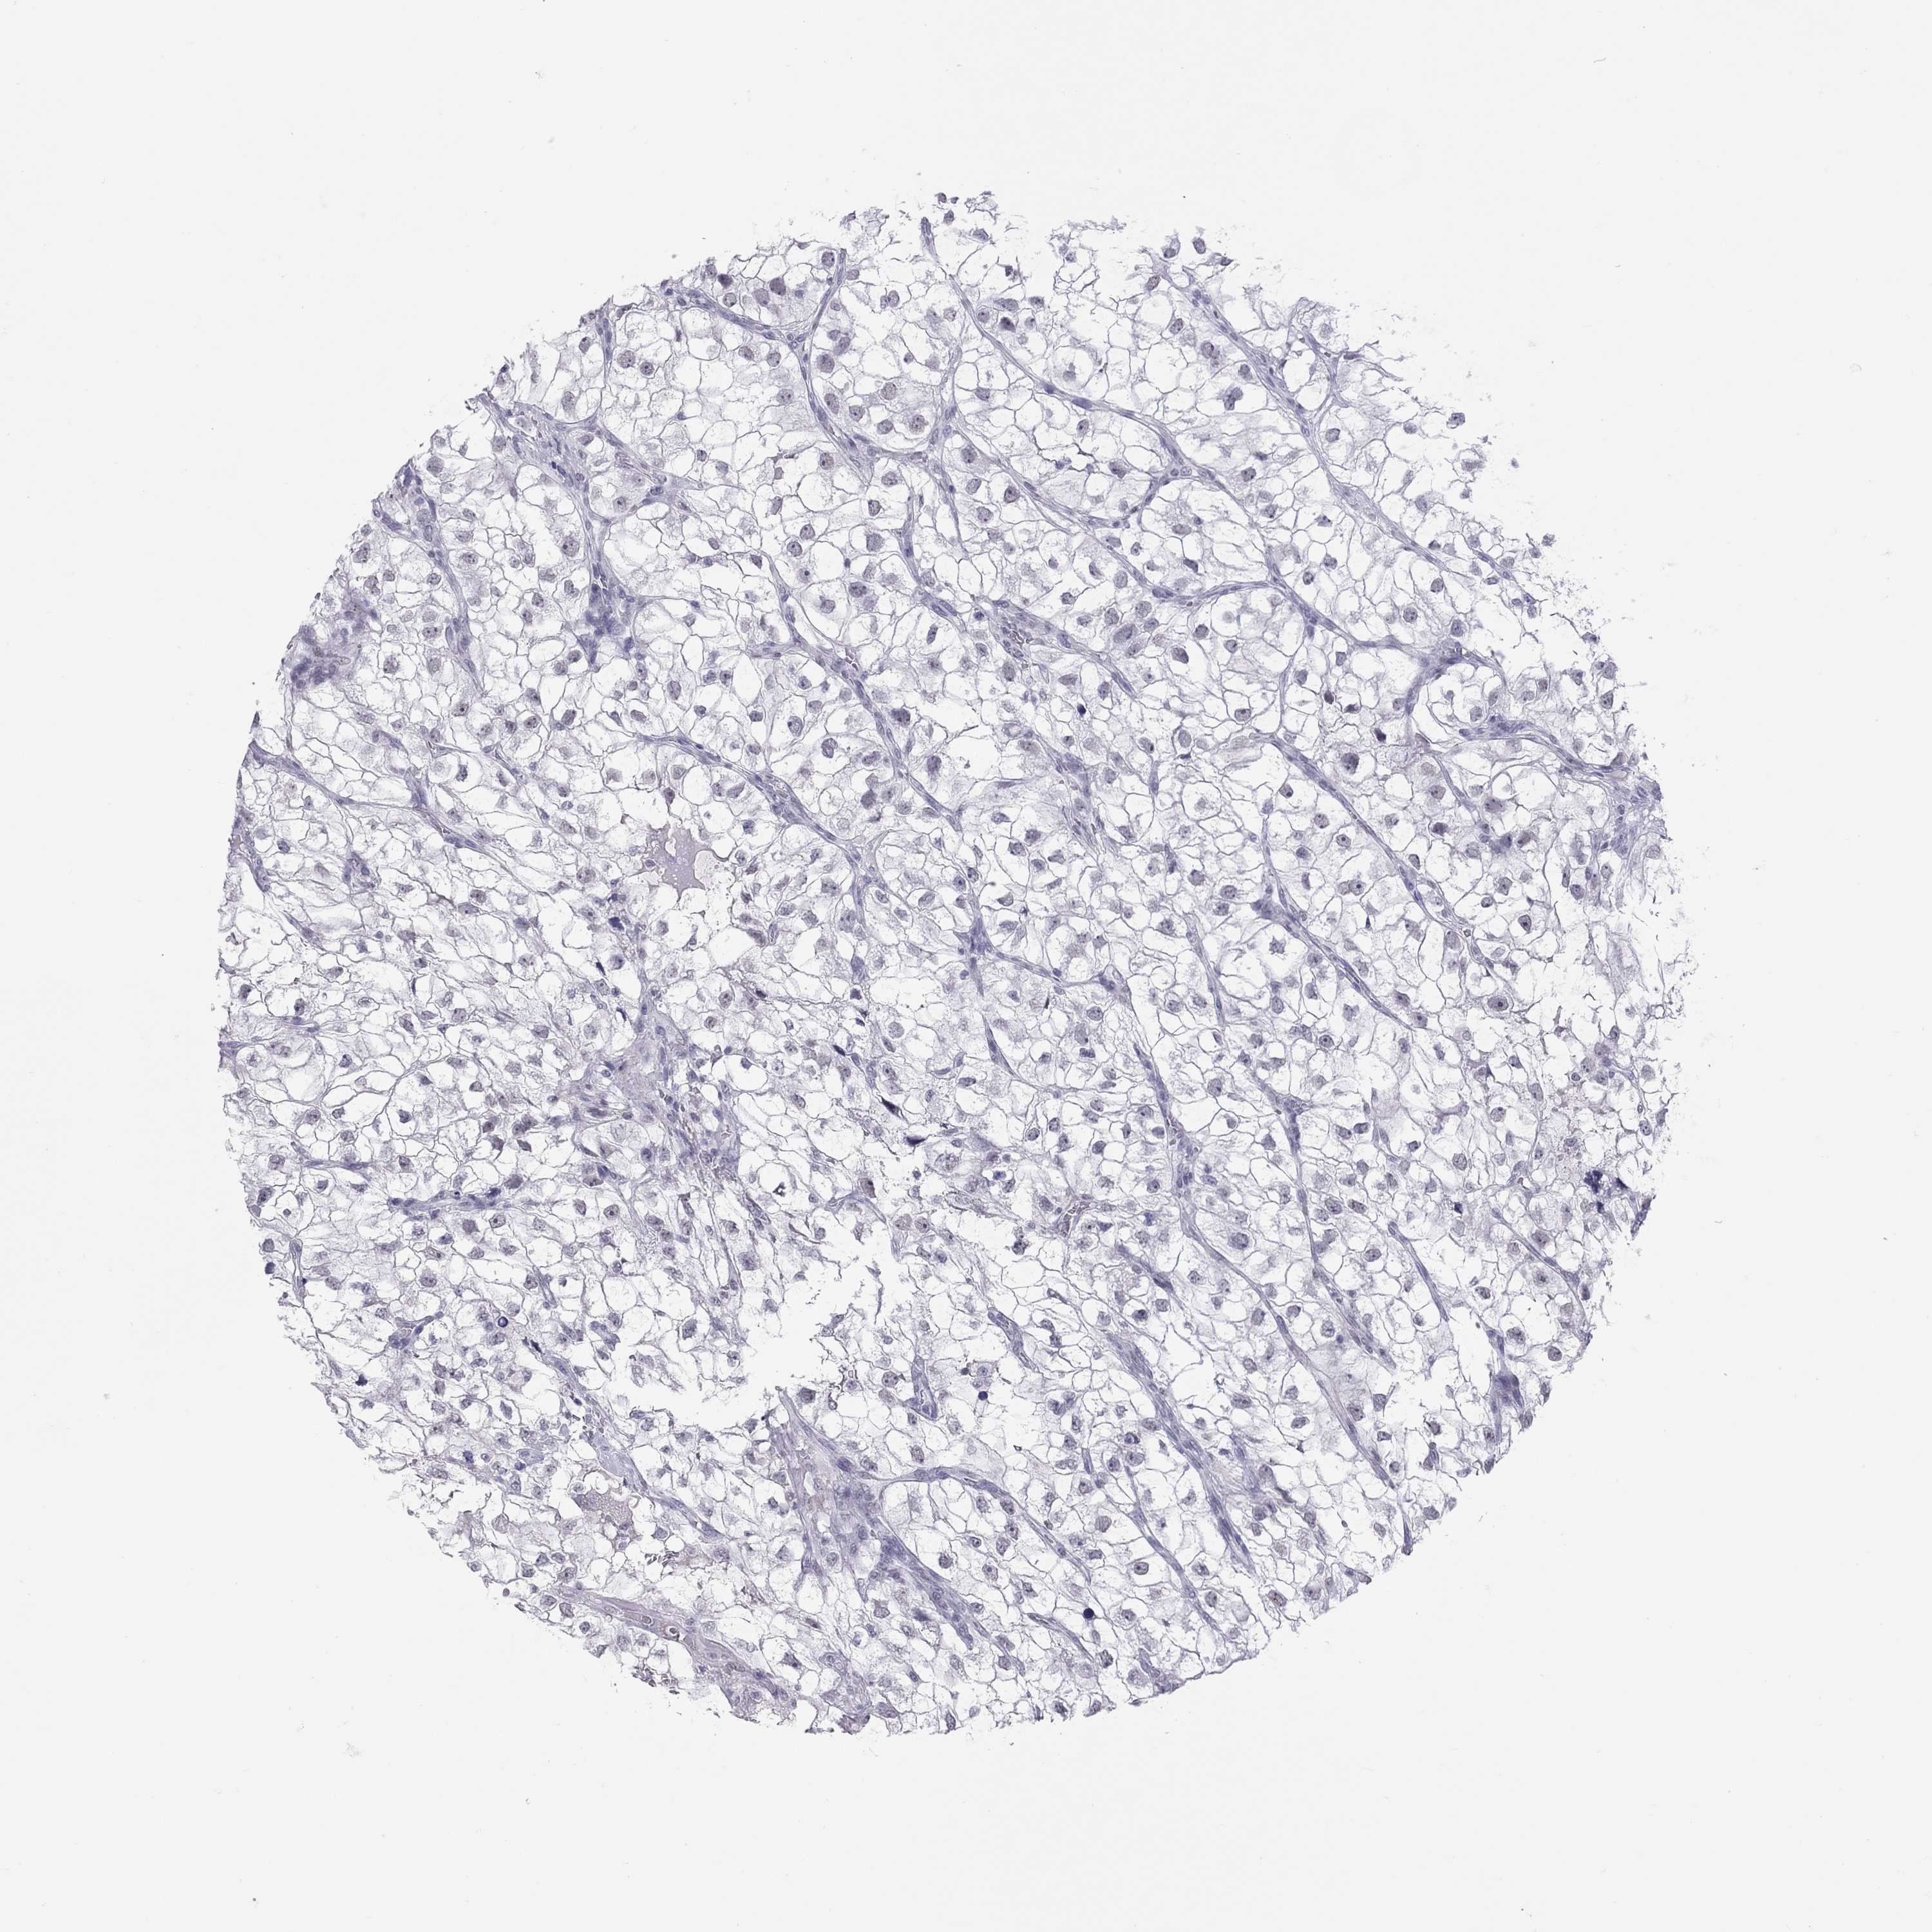

KICH TCGA KIRC TCGA KIRC VALIDATION KIRP TCGA PROTEIN RCC CPTAC PROTEIN EXPRESSION

Kidney renal clear cell carcinoma